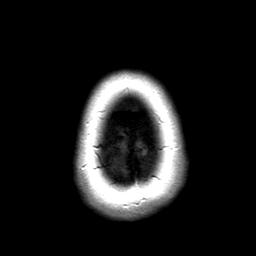

Cerebral hemorrhage, MR Study mr-pd -- Slice #23

[Home][Help][Clinical] Slice 23